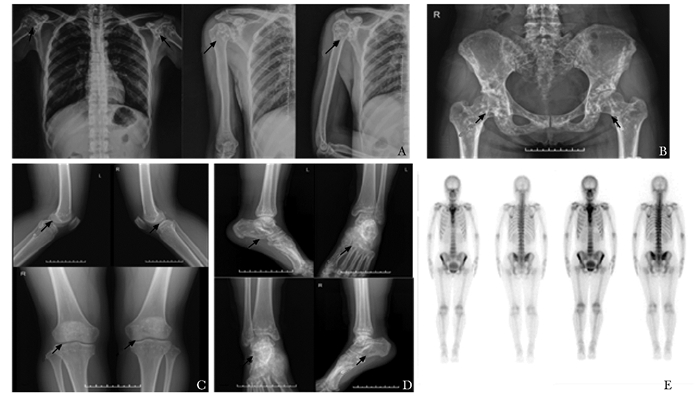

病历摘要患者,女,37岁,汉族,因体检X线胸片发现双肩病灶就诊。父母为非近亲结婚,家族中无类似病史。体格检查一般情况好,四肢关节活动自如,无压痛。骨骼X线片示:右肱骨、锁骨、肩胛骨及部分肋骨,骨盆诸骨,双膝关节诸骨以及双足踝均可见多发钙化病灶。全身骨核素显像未见异常(图 1)。采用双能X线吸收仪测定腰椎1-4和左侧股骨近端各部位骨密度Z值分别为L1-4:4.1,股骨颈:1.5和全髋部1.9。实验室生化检查:碱性磷酸酶(alkaline phosphatase,ALP)69 U/L,尿酸203 μmol/L,钙2.29 nmol/L,磷1.06 nmol/L。血清Ⅰ型胶原羧基端肽交联(beta C-terminal cross-linked telopeptides of type Ⅰ collagen,β-CTX)352.60 ng/L、骨钙素N端中分子(osteocalcin in the form of N-terminal midmole-cule fragment,N-MID)值14.92 μg/L、甲状旁腺素(parathyroid hormone,PTH)37.89 ng/L和25羟维生素D(25-hydroxy vitamin D,25OHD)13.46 μg/L, 以上生化检查结果均未见异常。根据该患者影像学检查分别在肩关节、髋部、膝关节、踝关节处发现骨内多发边缘清晰、密度均匀、大小不一的圆形或卵圆形钙化点,血钙、血磷、碱性磷酸酶和骨转换指标未见异常,拟诊为骨斑点症。因患者无不适未给予治疗。

| 图 1 患者骨骼影像学检查 Figure 1 Imaging examination of the patient A:右肱骨、锁骨、肩胛骨及部分肋骨骨密度异常(箭头);B:骨盆诸骨骨质内多发高密度影(箭头);C:双膝关节诸骨骨质多发高密度影(箭头);D:双足踝多发骨密度异常(箭头);E:核素显像未见异常放射性分布增高或减低 |